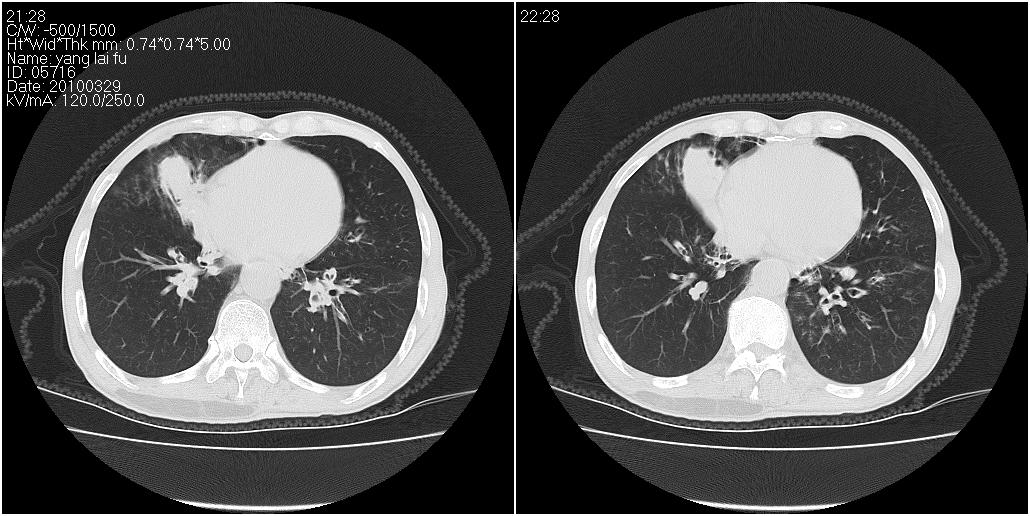

标题: ct增强:

右肺中叶阻塞性不张及肺炎,高度怀疑支气管占位,建议纤支镜检查!

考虑右肺中叶感染。左肺下叶支扩。

右中肺阻塞性炎症,建议纤支镜!双下支扩感染。

1)右肺中叶慢性炎症并支气管扩张,节段性肺不张。2)两肺下叶支气管扩张。